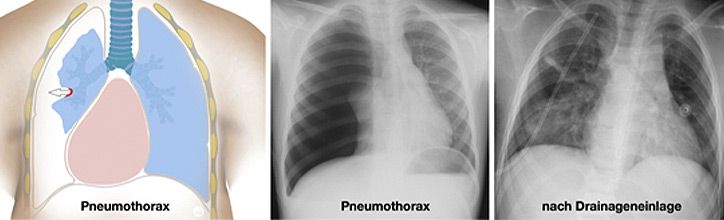

Thoraxtraumen betreffen sowohl den Weichteilmantel, das knöcherne Skelett (Rippen, Wirbelsäule) als auch die intrathorakalen Organe (V.a. Lunge, aber auch Speiseröhre, das Zwerchfell, die großen Gefäße und das Herz). Die Verletzungen können durch Verbrennungen entstehen, durch Verschlucken von Fremdkörpern oder giftiger Flüssigkeiten sowie durch stumpfe oder seltener spitze Gewalt. Beim eigentlichen Thoraxtrauma sind die inneren Organe betroffen, wobei es sich um ein schweres Krankheitsbild handelt, welches im Kindesalter dennoch in der Regel konservativ zu therapieren ist.

Grundlegender Unterschied beim Kind verglichen mit dem Erwachsenen, ist die geringere Körpergröße und Masse sowie die hohe Plastizität der knorpeligen Rippen. Diese frakturieren (brechen) beim stumpfen Thoraxtrauma in der Regel nicht, leiten aber die Kraft der Gewalteinwirkung vielmehr auf die darunter liegenden Strukturen fort. Folge können Gewebezerreissungen der Lungenstrukturen sein mit der Folge von Blutungen, Ödembildung, Pneumo- oder Hämatothorax (Abbildung)

Von der Geburt bis zur Pubertät vollzieht sich allerdings ein kontinuierlicher Reifungsprozess in den Lungen, so dass eine Organschädigung während dieses Zeitraums durch kompensatorisches Wachstum ausgeglichen werden kann.

Zum Zeitpunkt des Unfalls ist zu bedenken, dass der kindliche Organismus gegenüber einer Hypoxie (Sauerstoffunterversorgung) gefährdeter ist. Die Kompensationsfähigkeit der Lunge im Wachstumsalter ist vermindert, da bei geringerer funktioneller Residualkapazität ein höherer Sauerstoffverbrauch besteht. Die Überwachung von Kinder mit schweren Thoraxverletzungen muss deshalb auf einer spezialisierten kindertraumatologischen Intensivstation erfolgen und alle Therapiemöglichkeiten vorhalten.